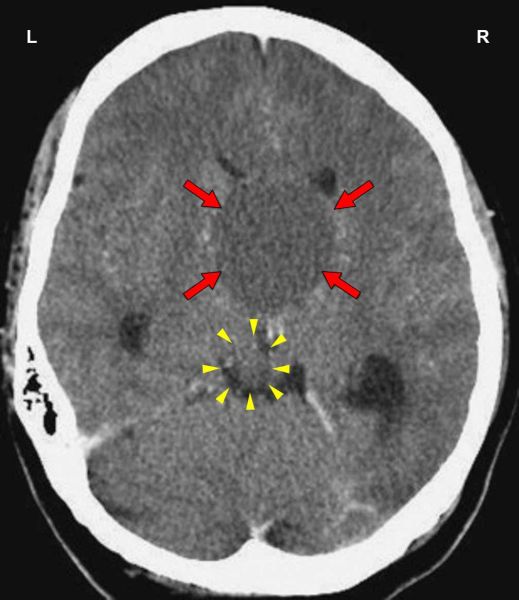

This CT scan presents a Hamer Focus in PCL-A with fluid accumulation (brain edema) in the control center of the olfactory nerves (red arrows - view the GNM diagram), indicating that the related conflict has been resolved. With water retention due to an active abandonment or existence conflict involving the kidney collecting tubules (yellow arrow), the brain edema increases significantly.